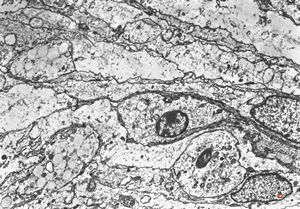

F,12y. | hypertrophic (onion bulb) neuropathy - n.suralis